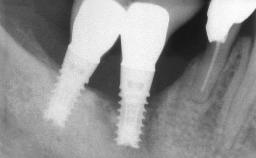

Excess Cement Resulting in Peri-implant Infection Presenting as a Draining Sinus Tract

Biological complications caused by undetected cement residue have been receiving much attention. Excess cement might be responsible not only for rapidly developing of peri-implantitis, but also for delayed or chronic manifestations of the disease many years after cementation (Wilson 2009; Linkevicius and coworkers 2013). Invitro and clinical studies have shown that it is very difficult or even impossible to completely clean up excess cement at subgingival margins, so popular in cemented restorations (Agar and coworkers 1997; Linkevicius and coworkers 2011, 2012). Possible outcomes of biological complications due to excess cement range from temporary inflammation of the peri-implant soft tissues without any serious esthetic and functional consequences all the way to implant loss. This report describes a case of peri-implantitis caused by residual cement; as well as the management and quite unusual resolution of the complication. The patient presented in 2009 with a draining sinus tract, tenderness on chewing, and tissue contact above the implant-supported restoration. The implant had been restored approximately three years before.

# of Implants 1

Type of Implants Two-Piece